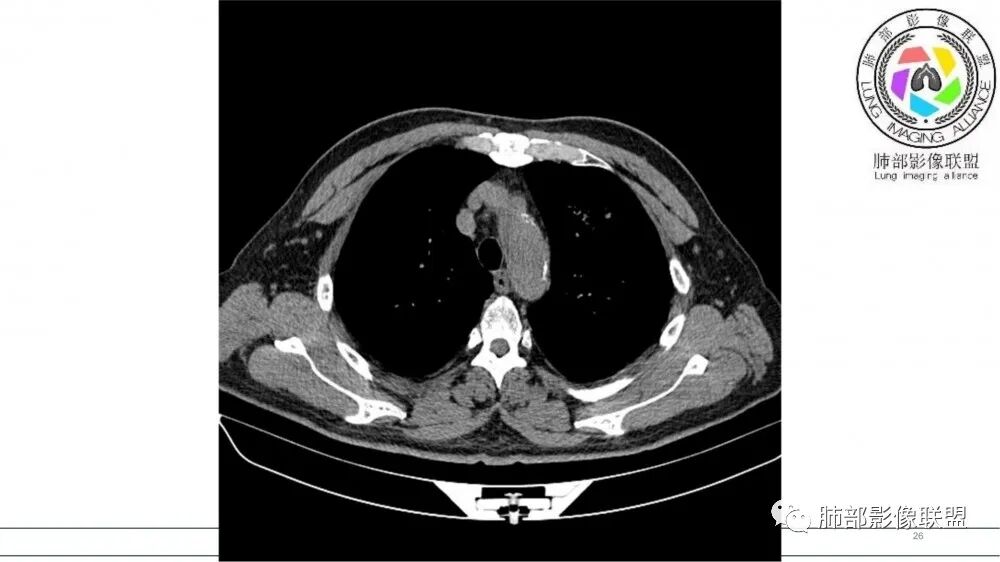

猜个鳞,沿支气管塑型生长,周围小花小草,肺门及纵隔淋巴结增大,吸烟老年男。鉴别TB

左肺上叶前段支气管内铸形生长软组织影,增强后均匀强化,远侧见斑片状磨玻璃影。考虑恶性病变,粘表?粘液腺?

考虑恶性占位,沿支气管塑型生长,增强未见明显强化,首先考虑鳞癌,鉴别APBA及结核,感觉不像,最后挂上小细胞肺癌。

病灶有强化,粘液栓不考虑。沿着支气管生长,远端小花小草,恶性首先考虑。鉴别结核

老年男性,左肺上叶前段支气管内铸形阴影,增强后病灶不均匀强化,内部有坏死?远端可见斑片状阴影(阻塞性肺炎)。考虑恶性病变,老年人,鳞?类癌?粘表不能排除。

左肺上叶前段支气管杵状指样扩张,内见实性组织阻塞性,并强化明显,边缘饱满,周边多发小斑点影,小花小草征,老年男性,长期吸烟史,方向恶性,首选支气管内浸润鳞Ca可能性大。

男,70岁,吸烟史,咳嗽,胸闷憋气一个月,左肺上叶不规则形软组织密度影,病灶沿支气管走形,周围见粟粒及棉絮样稍高密度影,增强扫描病灶内见少许坏死,考虑鳞癌可能,鉴别结核。

支气管壁病变

左肺上叶前段支气管管壁增厚,腔内软组织填充,有强化,远段阻塞性肺炎,考虑恶性

老年男性,肺气肿,吸烟史,左肺上支气管腔内铸型高密度影,呈指套状,远端多发树芽,增强不均匀强化,考虑鳞癌,鉴别小细胞癌

男性,吸烟,肿块沿左肺上叶支气管内生长,增强后病灶不均匀强化,考虑小细胞肺癌

70岁男,吸烟史,左肺上叶不规则肿块,轻度强化,前段支气管增厚,周围可见阻塞性小花小草,考虑鳞癌

老年男性,吸烟史,左肺上叶沿支气管塑型生长软组织肿块,轻度强化,周围小花小草,肺门及纵隔淋巴结增大,倾向恶性病变,鳞癌?粘表?

老年男性,吸烟史,左肺上叶支气管铸形,轻度强化,周围可见阻塞性小花小草,考虑鳞癌

B3指套征,常规不是鳞癌就是ABPA,有强化丶血管造影征,倾向于鳞癌

考虑恶性病变,血管指状改变,鳞癌或小细胞。

老年男性,左侧支气管腔塑形生长肿块,边缘可见多发小结节,增强后不均匀轻度强化,考虑恶性,鳞癌可能大,鉴别结核

病灶沿支气管生长,强化不均匀,坏死不明显,血管自然进入,支持恶性,小在先,鉴别淋巴瘤

老年男性,吸烟史,左肺上叶支气管塑形生长肿块,整体边缘较圆钝,不均匀强化,血管走形,形态较纤细,病灶远端可见花草样改变,恶性,先考虑小细胞癌鉴别鳞癌

老年男性,吸烟史,左肺上叶支气管铸形,变窄,轻度强化,周围阻塞性炎症,左肺门肿大淋巴结,考虑恶性,小细胞鉴别鳞癌

老年男性,影像支气管铸型,血管造影,考虑恶性,鳞癌,小细胞。

小花小草,支气管阻塞,考虑鳞癌,鉴别腺癌,结核,及淋巴瘤

老年吸烟男,左肺上叶支气管堵塞,远端小花小草,纵隔未见肿大淋巴结,考虑鳞癌,建议进一步支气管镜检查

左肺上叶支气管铸形生长,远端阻塞性炎症,增强后病灶有强化,坏死区明显。考虑中央型肺癌,鳞癌?小细胞癌?

左肺上叶尖后段支气管近端截断,远端见高密度铸型,远侧见阻塞性改变,老年男性,吸烟史,考虑恶性,鳞癌。ABPA代排

老年男性,吸烟史,左肺上叶不规则肿块,支气管铸型生长,增强轻度强化,周围可见阻塞性小花小草,考虑鳞癌

老年男性,长期吸烟史。左上肺前段沿支气管走形的指套样病变,增强可见病灶强化(排除结核、ABPA(也无气喘症状)),远端多发点状高密度影。考虑恶性肿瘤,鳞癌可能性大。

老年男性,左肺上叶支气管内铸形影,远端阻塞炎症,小花小草,轻度强化,考虑恶性病变,鳞?小?粘表不能排除。

老年男性,吸烟史,左肺上叶沿支气管生长指样影,边缘膨隆,轻度强化,周围斑点影,考虑恶性,鳞癌?

老年男,吸烟史,支气管铸形,有强化,恶性考虑,小细胞?鳞癌?粘表?结核,ABPA鉴别

指套征明确吧

有强化吧,淋巴结大

恶性

指套征,扩张支气管内软组织强化,远侧肺野阻塞性炎,纵隔、左肺门肿大淋巴结;老年男性,吸烟,考虑鳞癌,鉴别小

小花小草,铸型粘液拴,左上叶支气管壁增厚,腔内可见软组织结节,粘液无强化,伴随血管粗细不均,老年,吸烟,定性恶性,磷癌

老年男性,术前检查肺气肿背景,左肺上叶结节,沿支气管蠕虫样生长,左肺门及纵隔淋巴结肿大,增强扫描不均匀强化,血管包绕,结合吸烟史,考虑小细胞肺癌。

老年吸烟男性,尖前段支气管内塑形生长,增粗蠕虫样,没有肺不张(排除鳞癌?),远端少许阻塞肺炎,增强低强化,锁定小

老年男性,吸烟,指套征,蠕虫征,阻塞性炎症不严重。可见血管穿行,密度均匀,轻度强化,首先考虑小细胞肺癌。鉴别鳞